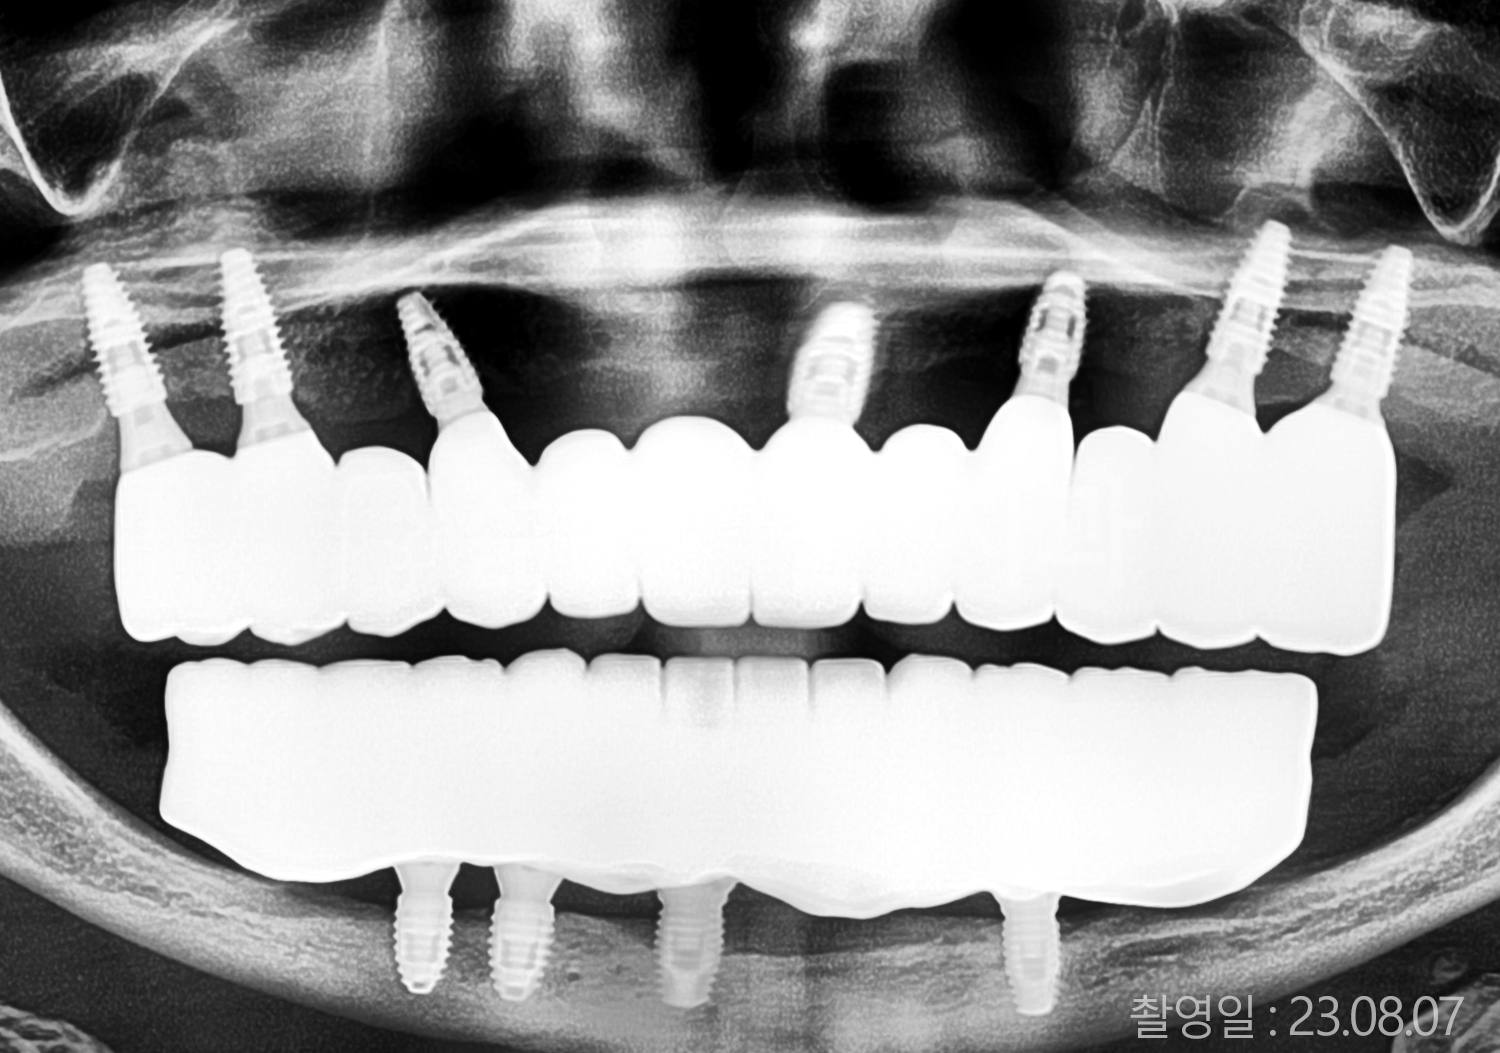

• 50대 고혈압, 당뇨, 고지혈증 전체치아 10개 이상 임플란트

• 60대 골다골증, 간경화 전체치아 10개 이상 임플란트

• 60대 고혈압, 고지혈증 전체치아 10개 이상 임플란트

• 50대 고혈압, 당뇨 전체치아 10개 이상 임플란트

• 60대 고혈압 전체치아 10개 이상 임플란트

• 60대 전체치아 10개 이상 임플란트

• 60대 고지혈증 전체치아 10개 이상 임플란트

• 40대 전체치아 10개 이상 임플란트

• 70대 전체치아 10개 이상 임플란트